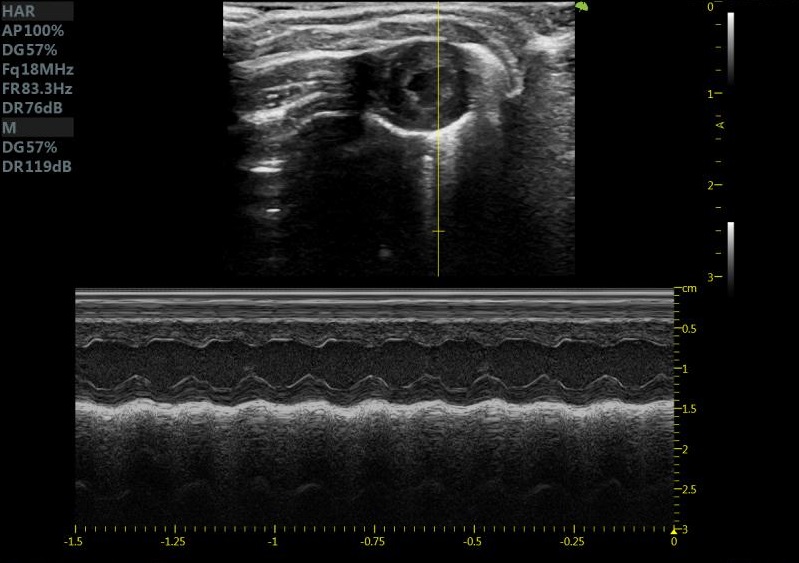

小鼠长轴M型 小鼠短轴M型

大鼠短轴M型 大鼠长轴M型